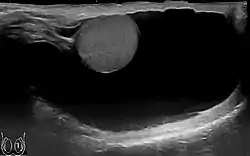

Communicating hydrocele, caused by the failure of the processus vaginalis closure.